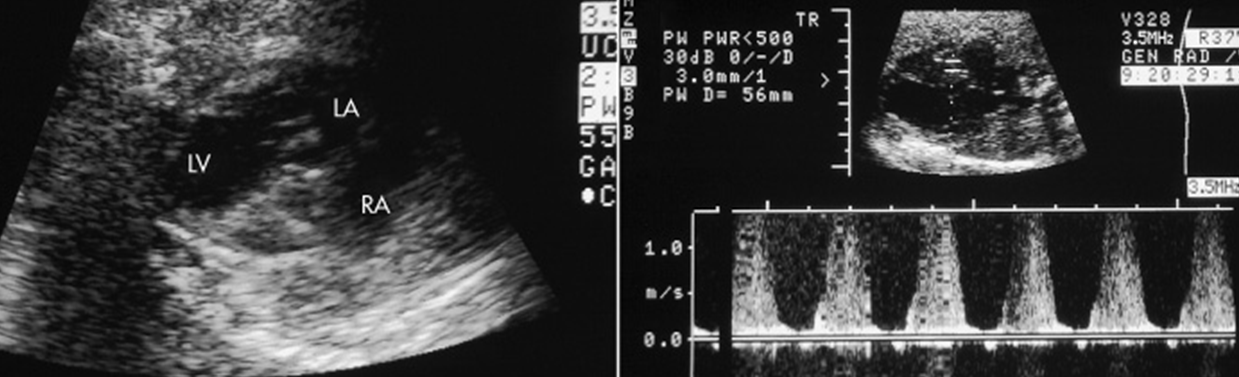

When a pulmonic stenosis is present, what is seen on US.

Cusps become thickened

Less mobile

Domed (in diastole)

When a Pulmonic Stenosis, what else may be seen?

Hypoplastic or may have poststenotic dilation

May see dilated RA & RV